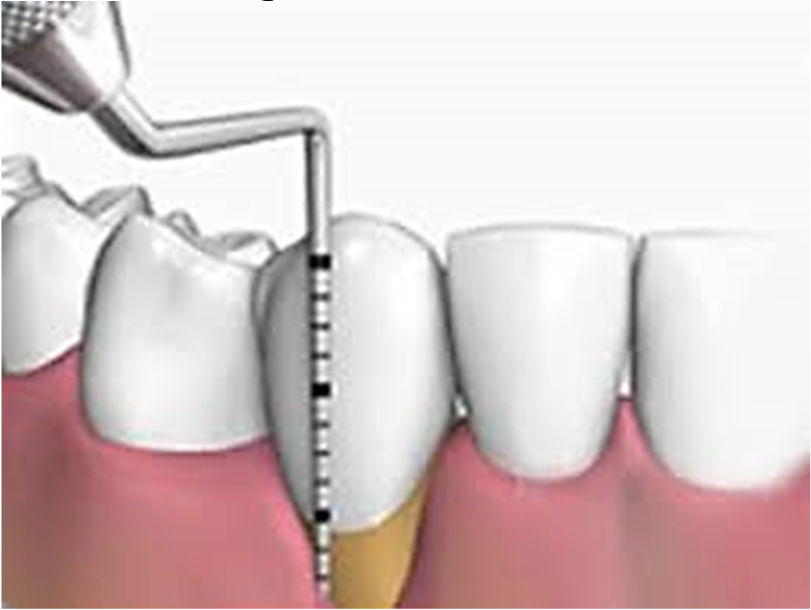

Considere a imagem abaixo:

Aliado ao exame clínico visual, o principal exame para detectar a presença da doença periodontal é: